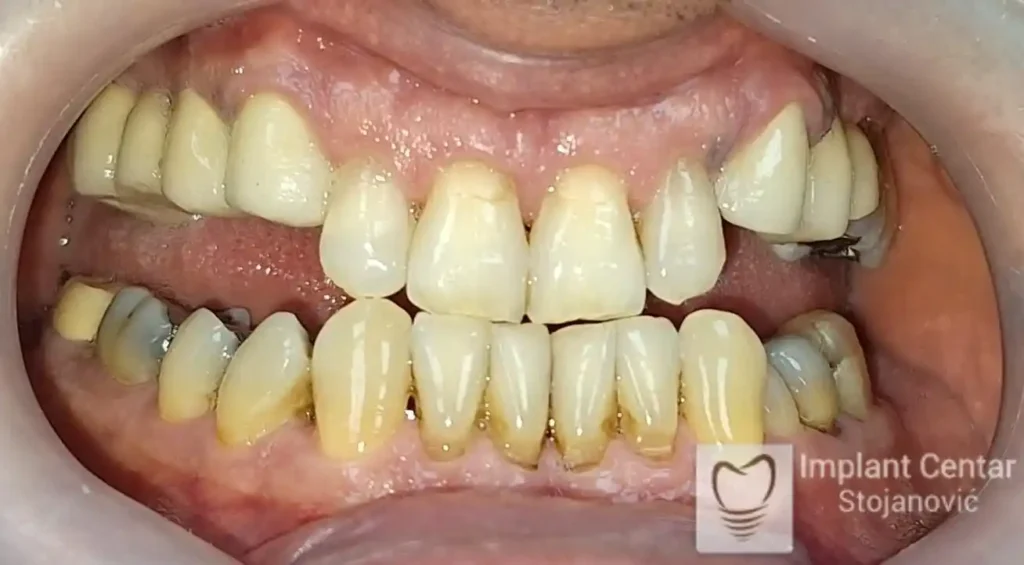

Pacijent sa rascepom usne, nepca i alveolarnog grebena uspešno je rehabilitovan fiksnim protetskim radom na implantatima. Pre dolaska u našu ordinaciju, pacijent je u gornjoj vilici nosio totalnu protezu preko preostalih zuba, dok je u donjoj vilici bio zbrinut parcijalnom mobilnom protezom. Tokom višegodišnje potrage za adekvatnim rešenjem, pacijent nije uspeo da pronađe zadovoljavajuću terapijsku opciju ni u zemlji ni u inostranstvu.

Nakon detaljnog kliničkog pregleda i analize radioloških snimaka, izrađen je sveobuhvatan plan terapije sa ciljem uklanjanja mobilnih proteza i postizanja maksimalne funkcionalne i estetske rehabilitacije. Zbog loše biološke vrednosti preostalih zuba, doneta je odluka o njihovom vađenju i ugradnji dentalnih implantata.